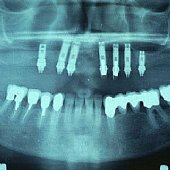

Bilder: Zahnimplantate bei Zahnlosigkeit im Unterkiefer

• Röntgendarstellung einer fest sitzenden Unterkieferbrücke mit 5 Implantaten.